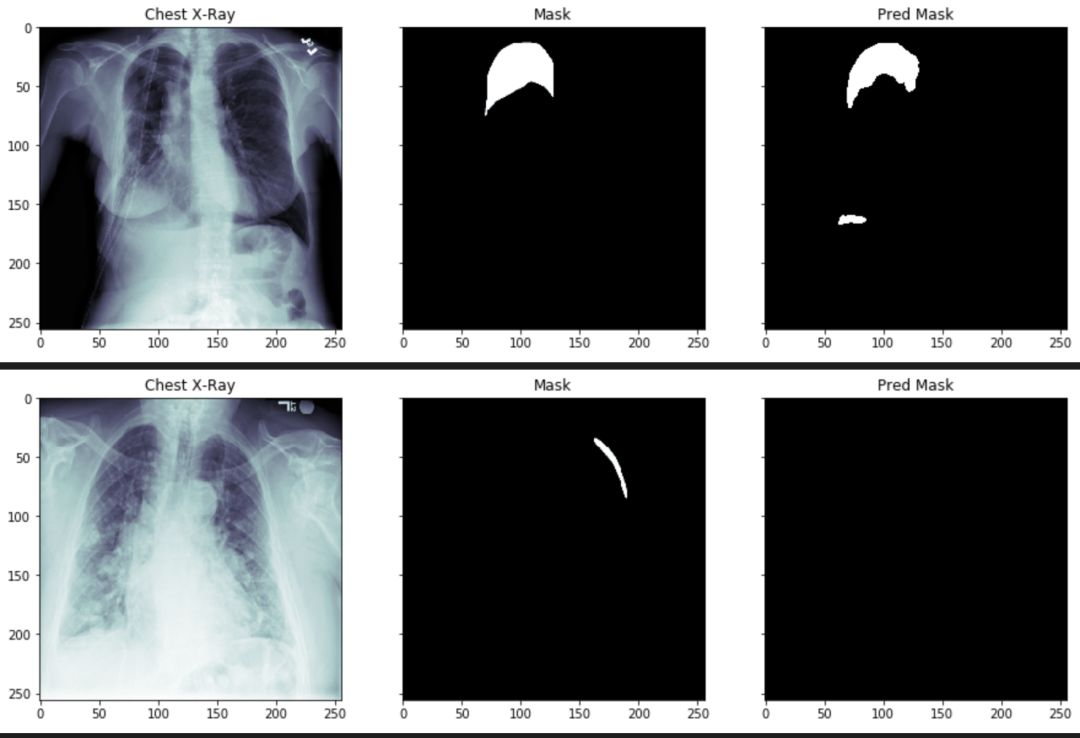

count = 0

for i in range(0,30):

if count <= 15:

x, y = validation_generator.__getitem__(i)

predictions = model.predict(x)

for idx, val in enumerate(x):

if y[idx].sum() > 0 and count <= 15:

img = np.reshape(x[idx]* 255, (img_size, img_size))

mask = np.reshape(y[idx]* 255, (img_size, img_size))

pred = np.reshape(predictions[idx], (img_size, img_size))

pred = pred > 0.5

pred = pred * 255

plot_train(img, mask, pred)

count += 1

通过上述图片,我们可以看到气胸的阴影面积和位置,已经被分离出来了。但是,某些参数还需要进一步的调整。